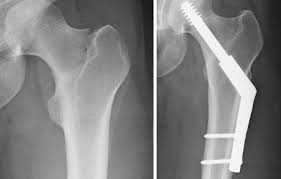

Hip stress fracture treatment. Hip fractures are usually treated in hospital with surgery. Some cases of hip stress fractures require surgery whereas some others can be treated without the need for surgery. Depending on the severity of the hip stress fracture surgery may be.

If an x-ray or MRI at the sports clinic confirms that youre experiencing a stress fracture in the hip the doctor will likely instruct you to rest. There are different operations which are. This depends on the fracture site and whether it is a simple crack or a displaced fracture.

What would a physiotherapy treatment for a Hip Stress Fracture involve. Most people will need surgery to fix the fracture or replace all or part of their hip ideally on the same day theyre admitted to hospital or the day after. Treatment of hip stress fracture Immediately after a stress fracture is diagnosed the patient should discontinue all sports activities and walk with two crutches to apply less forces to the injured leg.

Stress fractures under the femoral neck are less likely to be displaced and therefore they are usually treated by nonsurgical procedures. Treatment for hip fracture usually involves a combination of surgery rehabilitation and medication. Stop any moderate activity and repetitive stressful exercises running squatting cycling.

Medications for Stress Fractures You can take over-the-counter medications to manage pain. Initial treatment of a hip stress fracture may include X-rays a magnetic resonance imaging MRI scan or a bone scan to further evaluate your condition.